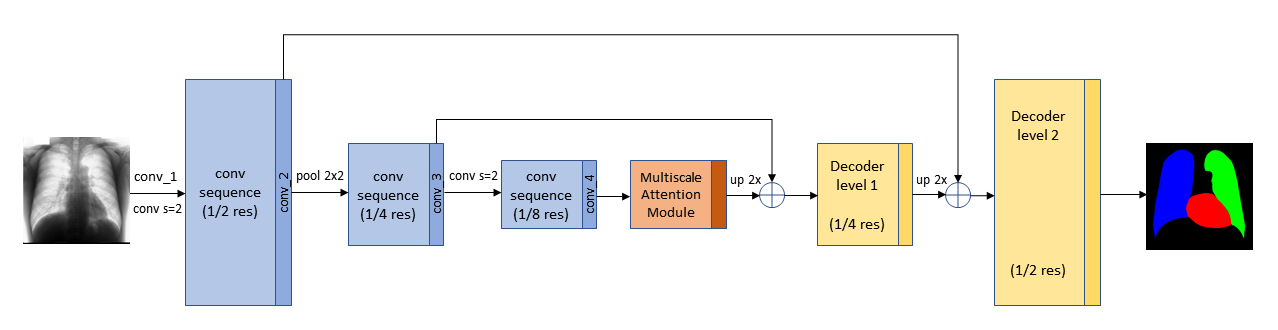

In this paper, the Segmentation Multiscale Attention Network (SMANet) [15] has been employed. The SMANet is composed by three main components, a ResNet encoder, a multi–scale attention module, and a convolutional decoder (see Figure 4).

This architecture, initially proposed for scene text segmentation, is based on the Pyramid Scene Parsing Network (PSPNet) [11], a deep fully convolutional neural network with a ResNet [61] encoder. Dilated convolutions (i.e. atrous convolutions [62]) are used in the Resnet backbone, to widen the receptive field of the neural network in order to avoid an excessive reduction of the spatial resolution due to down–sampling. The most characteristic part of the PSPNet architecture is the pyramid pooling module (PSP), which is employed to capture features at different scale in the image. In the SMANet, the PSP module is replaced with a multi–scale attention mechanism to better focus on the relevant objects present in the image. Finally, a two–level convolutional decoder is added to the architecture to improve the recognition of small objects.